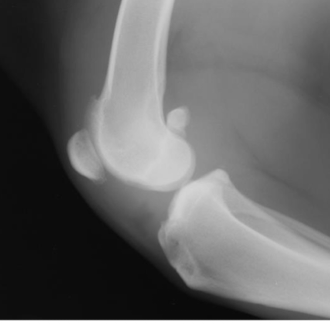

What is the arrow pointing to?

large osteophyte on the anconeal process (earliest change seen in DJD)

osteophyte on the medial coronoid process in elbow DJD